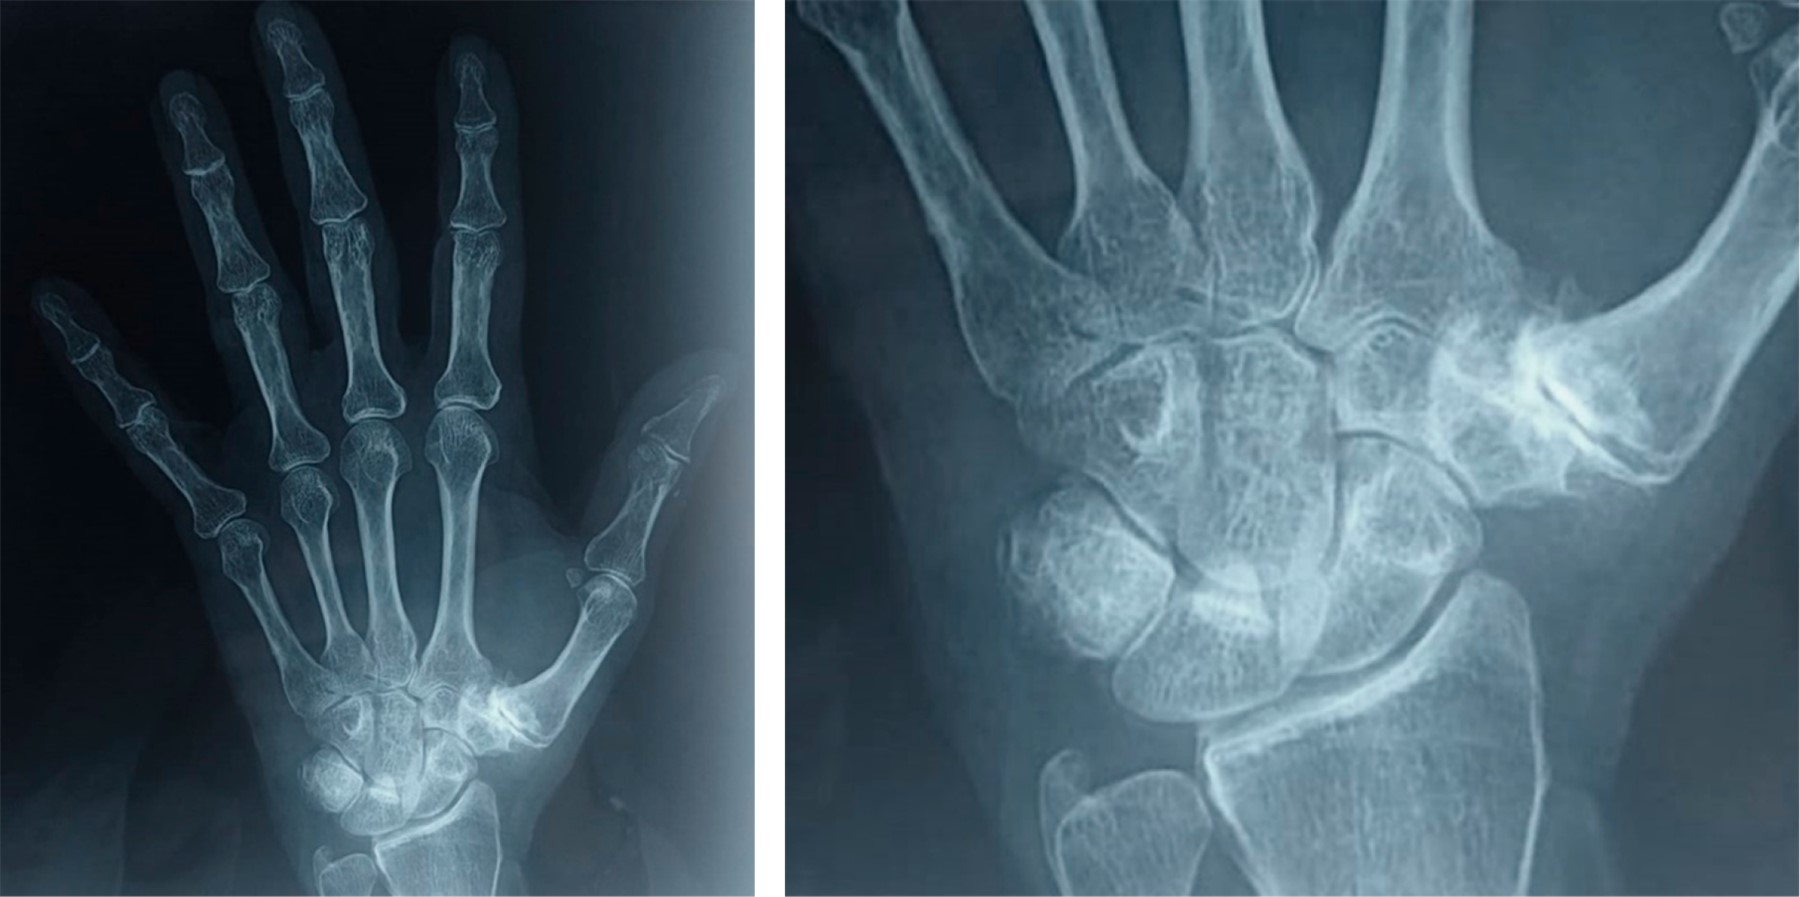

La artrosis trapecio-metacarpiana o rizartrosis es una patología que produce dolor, disminución de la fuerza y pérdida de destreza en la movilidad del pulgar, limitando la función global de la mano. Afecta a 20% de la población mayor de 50 años, principalmente en la mujer; provoca desgaste crónico y progresivo del cartílago que, en la mayoría de los casos, ocurre en ambas manos. Son típicos los episodios de dolor intenso en la base del pulgar que aumentan al movimiento y al realizar esfuerzos con la mano. Los movimientos del pulgar se reducen, lo que ocasiona rigidez progresiva. En los casos avanzados, se aprecia deformación por inestabilidad, subluxación y formación de osteofitos (Figura 1). La radiografía simple permite corroborar el diagnóstico utilizando la clasificación por estadios de Eaton y Littler (Tabla 1). Cuando el tratamiento médico conservador resulta ineficaz, se recurre a la cirugía. La finalidad de la prótesis trapecio-metacarpiana es eliminar el dolor y restaurar la longitud del pulgar, la fuerza y funcionalidad (Figura 2). El procedimiento quirúrgico por lo general se realiza de forma ambulatoria, consiste en eliminar la porción del hueso que está desgastada y reemplazarla con la prótesis, la recuperación es rápida y en dos o tres semanas se inicia la rehabilitación.

Figura 2